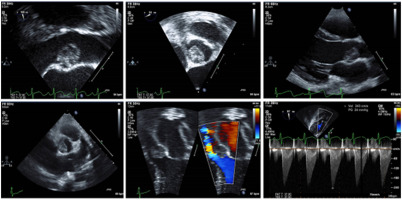

The latest issue of CASE is now available with intriguing reports, including “Aortic Valve Myxoma in a Young Child.” CASE Editor-in-Chief Vincent Sorrell, MD, FASE, remarked, “Masses in the heart are relatively common and the learned echocardiographer is aware of the many characteristic features to help create a differential diagnosis, recognizing that, in the end, a final diagnosis requires tissue. Most importantly, categorization as a benign (often normal variant or embryologic remnant) or a pathologic mass is the first step. Once the visualized mass is established as pathologic, then the clinical setting (patient characteristics, signs, and symptoms) is essential to drive further testing or treatment. These authors present a fascinating case of a five-year-old, asymptomatic girl with a murmur found to have a very unusual, large (> 1.0 cm) mass attached to the ventricular surface of the aortic valve non-coronary cusp. The authors provide excellent images and walk the reader through their consideration for potential etiologies (including Carney complex) and role for advanced imaging. Given the size of the mass and partial obstruction (transvalvular gradient nearly 25mmHg) surgery was performed and confirmed that the mass was a myxoma. This is another nice example of how CASE reports can help expand our diagnostic considerations.”